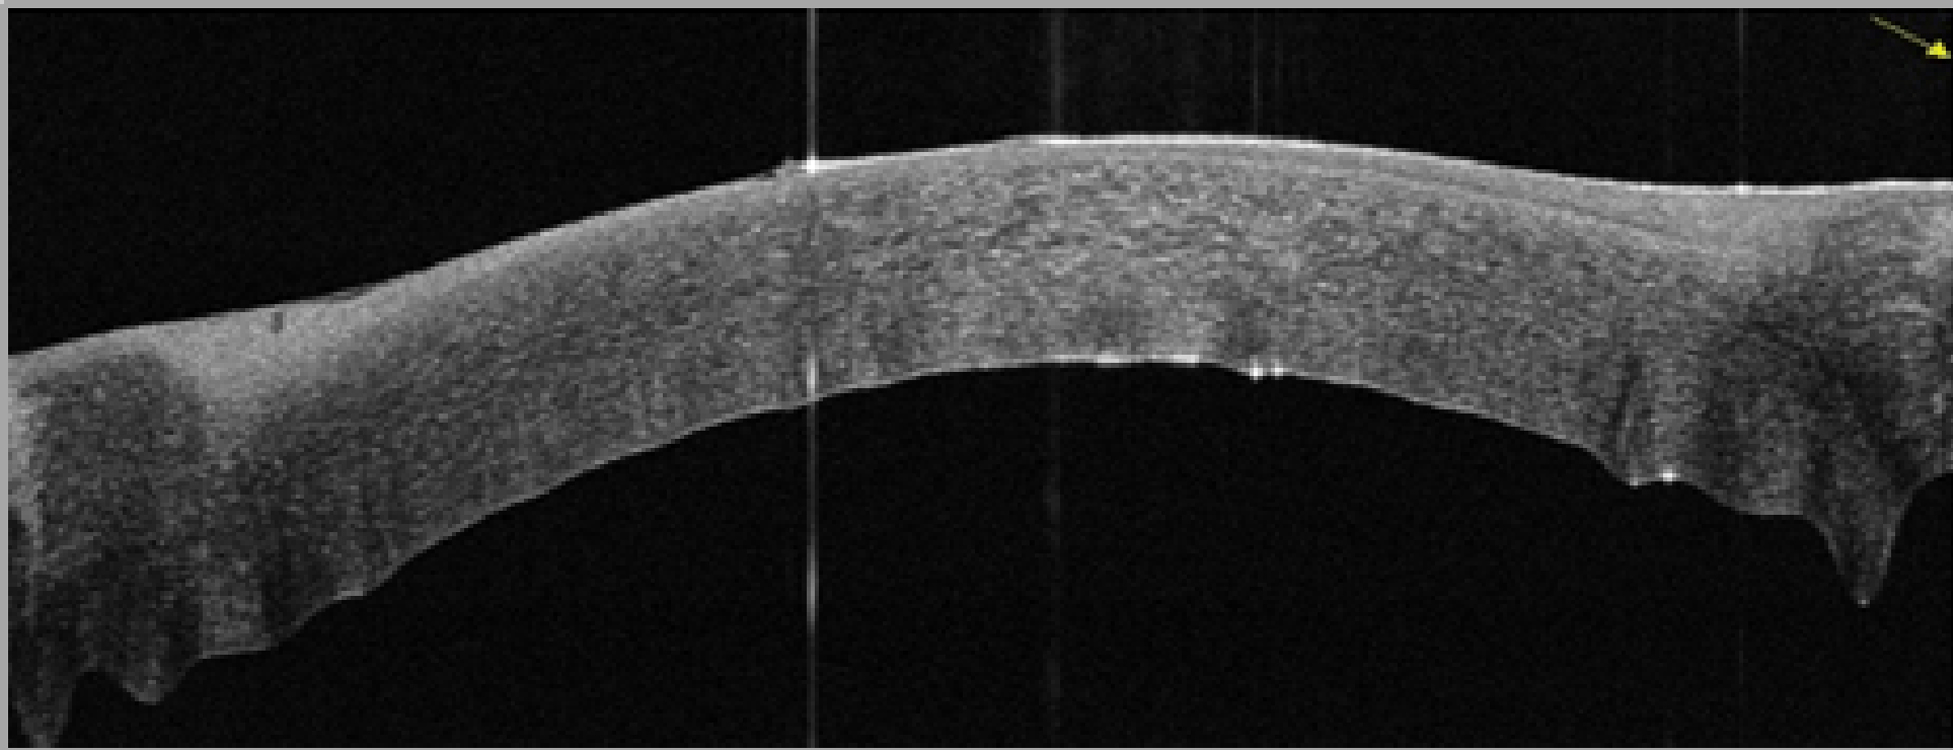

Говоря об анатомо-морфологических особенностях послеоперационных изменений роговицы в результате применения модифицированной методики ФРАК, следует отметить более равномерный задний профиль в центральной зоне роговицы на полученных снимках оптической когерентной томографии, отсутствие «складчатости» задней поверхности. Добавление обвивного шва в сравнении с ранее предложенной методикой ФРАК, где использовали узловые швы (рисунок 2), позволило обеспечить более равномерное натяжение роговичной ткани, тем самым не только избежать «волнистости» заднего профиля роговицы, но и уменьшить послеоперационный астигматизм (рисунок 3).

Рисунок 2. Скан ОКТ переднего отрезка глаза: «волнистость» заднего профиля роговицы (шовная фиксация узловыми швами).

Figure 2. OCT scan of the anterior segment of the eye: "waviness" of the posterior corneal profile (suture fixation with interrupted sutures).

Рисунок 3. Скан ОКТ переднего отрезка глаза: равномерный задний профиль в центральной зоне роговицы (комбинированная шовная фиксация).

Figure 3. OCT scan of the anterior segment of the eye: uniform posterior profile in the central area of the cornea (combined suture fixation).